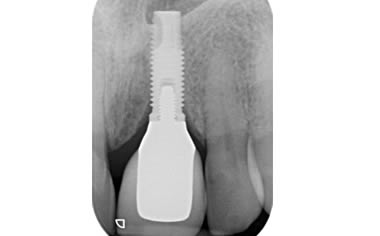

More front teeth replaced by dental implants

Case Three (4 images)